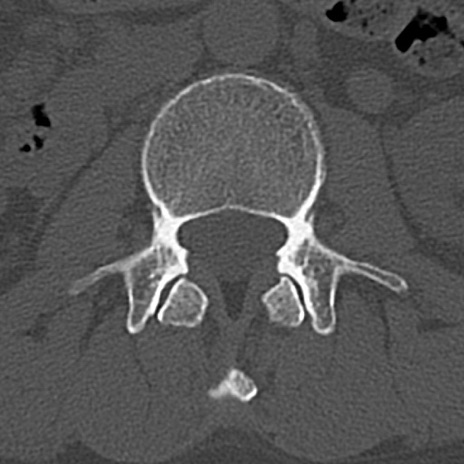

腰椎CT

横断像と矢状断像